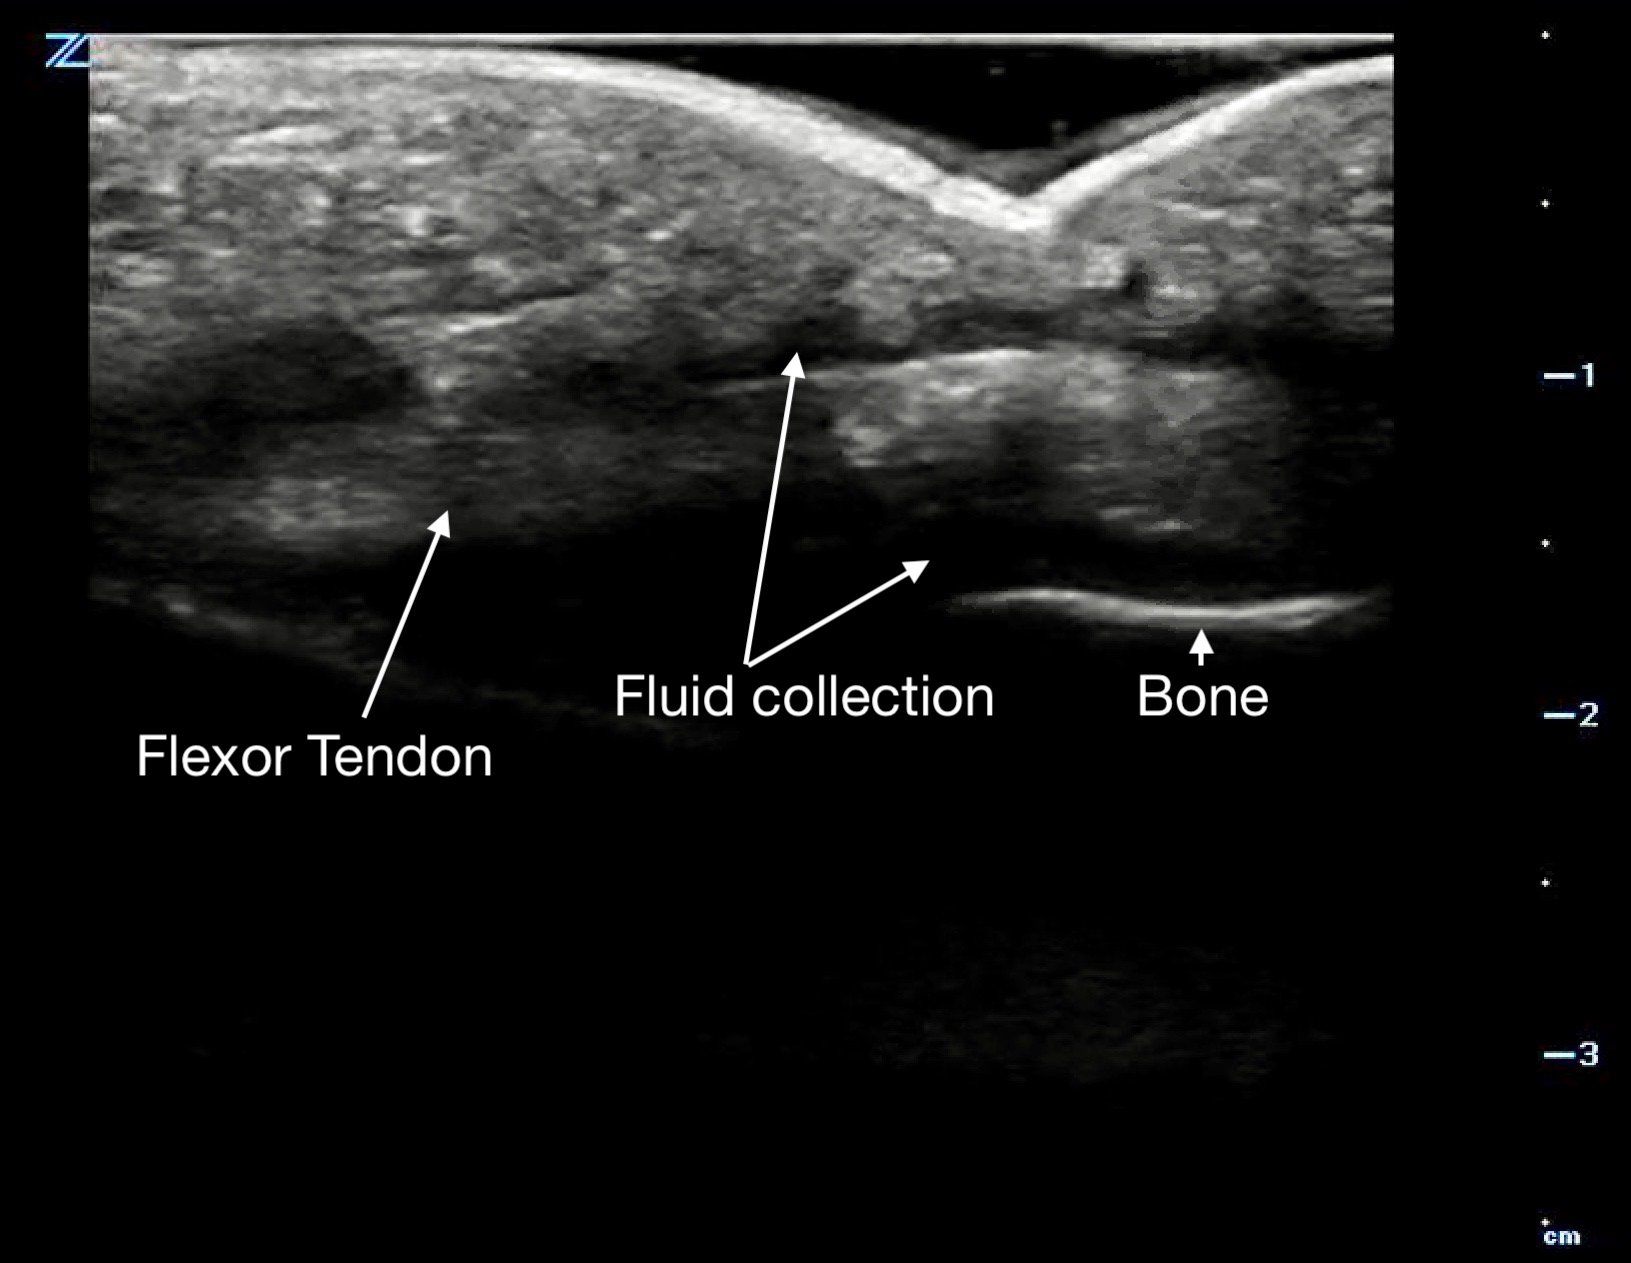

Tenosynovitis will appear as a thickened tendon and on short axis will have a halo of anechoic fluid surrounding it in the tendon sheath.

Figure 14a.

Figure 14b.

a long axis view with fluid above and below the flexor tendon.